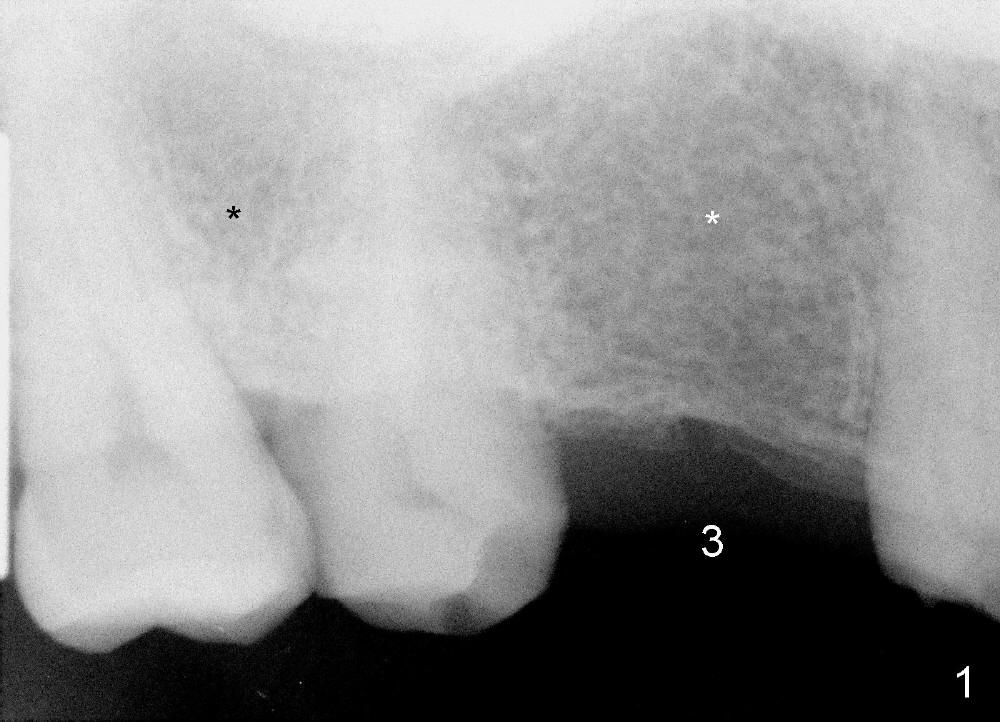

The bone density (Fig.1 white *) at the edentulous area (#3) is lower than that at the dentulous one (black *, 50 year-old man). The buccal plate is also atrophic and concave (Fig.2,3 arrowheads). A series of bone expanders are used to form osteotomy (following 1.6 mm pilot drill) at the depth of 14 mm (Fig.3 E 3.0 mm in diameter). When the last expander (4.3 mm) is removed from the osteotomy, the buccal plate appears to have been moved buccally (Fig.5 arrowheads). A 5.3x14 mm submerged implant (Fig.6 I) is placed with insertion torque >35 Ncm. The buccal plate seems to improve following placement of an 8.2 mm healing abutment and suturing (Fig.7). No bone graft is used. The buccal plate remains normal 12 days postop (Fig.8). It is slightly concave 3 months postop (Fig.9) with minimal bone resorption at the crest (Fig.10 (H: healing abutment),11 (A: cemented abutment). Nine months post cementation (12 months postop), bone resorption at the crest remains minimal (Fig.12) while the buccal plate (Fig.13 *) at #3 remains strong. Bone loss appears not to get worse 22 months post cementation (Fig.14). Soft and hard tissues remain healthy around the implant crown 3 years (Fig.15) and 3.5 years (Fig.16,17) post cementation.